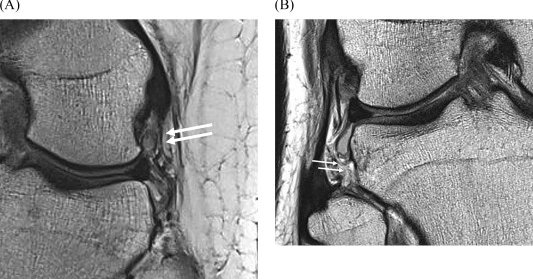

Repairing horizontal meniscal tears with an outside-in vertical suture technique showed good healing on serial MRI. Meniscus shape initially became trapezoidal post-op but remodeled toward a normal triangular shape by 2 years. https://t.co/e2sabL8Nuw